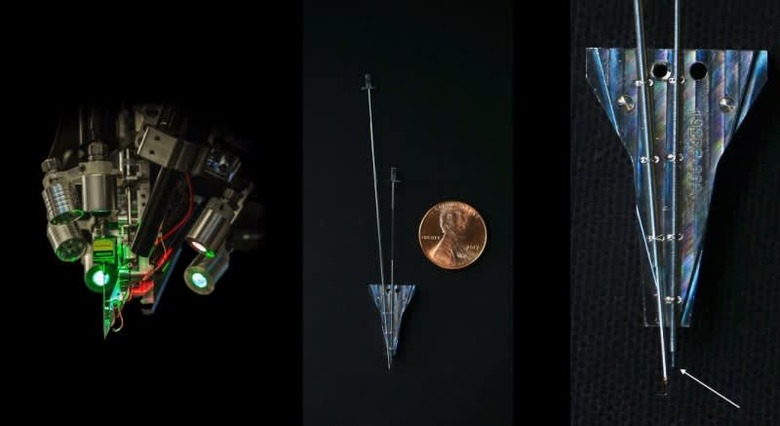

One big reveal is that it "hopes" to begin working on human subjects as soon as the second quarter of next year. In the picture above, that was shown during the presentation, that small protrusion at the bottom right with the arrow pointing to it, is the size of the thread that it actually hopes to implant.

According to the article, its bundles of flexible threads are about one quarter the diameter of a human hair, implanted using needles to avoid blood vessels on the brain's surface. Then the embedded sensors capture information and send it to a receiver (the chip above) on the surface of the skull. From there it transmits wirelessly — Elon Musk said it could Bluetooth the information to your skull. Right now implantation requires drilling holes, but researchers hope in the future they can use lasers to avoid "unpleasant" vibration.

Neuralink president Max Hodak went on to explain why it's embedding sensors directly into the brain, near but not in neurons. Simply, it's the only way to send and receive the information necessary, from "spikes" of activity. A neurosurgeon is also part of the presentation, showing off some videos of the implantation technology, and how its robot can install thousands of wires directly into the brain while avoiding tissue damage and bleeding. Eventually, they'd like to do it without shaving the patient's head, although he acknowledged that the first operations will be more like current deep brain implants.